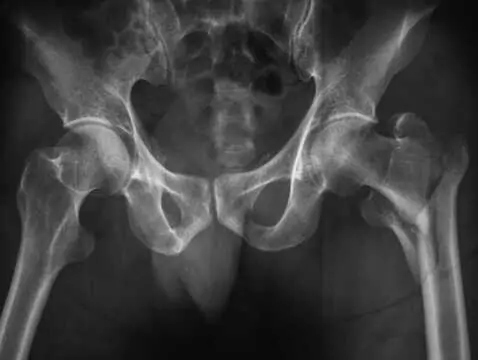

Zwiększona podatność układu kostnego na złamania i zniekształcenia objawiająca się w okresie menopauzy.

Wzrost poniżej 150 cm. Najczęściej połączony z charakterystycznie zmienioną sylwetką ciała oraz wadami narządów wewnętrznych, może sugerować występowanie tzw. zespołu Turnera. Zespół Turnera jest to...